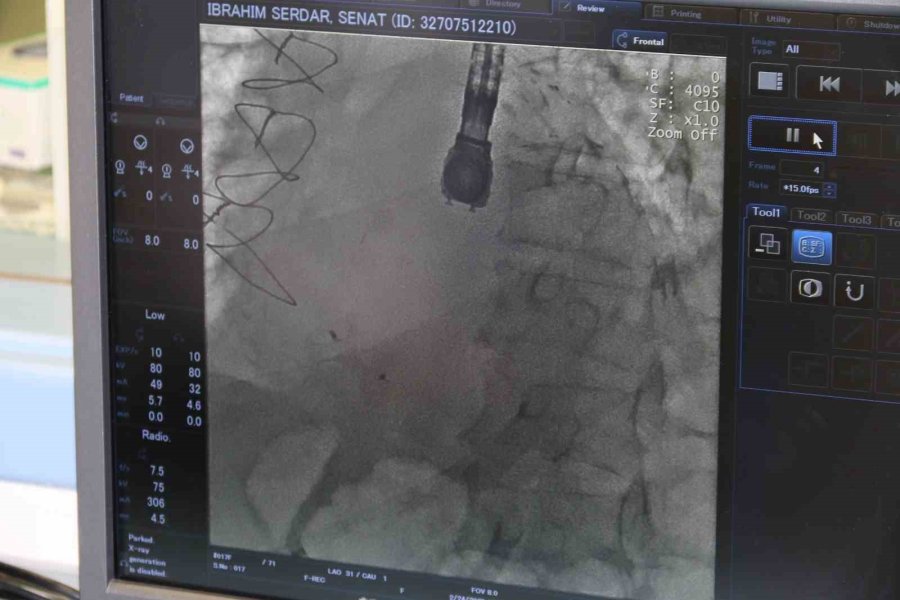

Kardiyoloji Uzmanı Dr. Bektaş Murat, kronik rahatsızlıkları olan ve bunların ameliyatı zorlaştıracağını öngörerek ameliyat kararı aldı. Anjiyografi adlı yöntemle kasıktan girerek kalpteki deliği uzun ve meşakkatli süren ameliyat sonrası kalpteki delik kapatılmış oldu. Ameliyat sonrası durumu takip edilen hasta, taburcu edildi. Böylelikle 68 yaşındaki İbrahim Serdar Şenat, bu operasyonu geçirip de yaşayan 9 hastadan biri oldu.

Operasyonla alakalı konuşan Eskişehir Şehir Hastanesi'nde görevli Kardiyoloji Uzmanı Dr. Bektaş Murat, "Hastamız polikliniğimize nefes darlığı ve kalp yetersizliği semptomuyla başvurdu. Ancak hastamızın hikâyesini aldığımızda yaklaşık 20 gün önce başka bir merkezde kalp krizi geçirdiğini ve anjiyografiyle tedavi edildiğini öğrendik. Muayene sırasında kalp kriziyle beraber ortaya çıkan, kalp karıncıklarının duvarında VSD dediğimiz bir kalp deliğinin meydana geldiğini öğrendik. Bu gerçekten çok ciddi bir durum. Kalp krizine bağlı olarak çok nadir bir şekilde gerçekleşiyor; ancak nadir gelişse de ölümcül olabilen bir hastalık. Dolayısıyla bu gelişen komplikasyonu hızlı bir şekilde tedavi etmemiz gerekiyordu. Onun için hastamızı yoğun bakıma yatırdık ve ileri tetkiklerini yaptık. İleri tetkikler sonucunda "Ventriküler Septal Defekt" (VSD) dediğimiz bu hastalığın, kalp krizine bağlı olarak geliştiğini ve kalbin duvarında delik şeklinde olduğunu tespit ettik. Hastanemizdeki kalp ekibiyle de hemen bir istişare yaparak tedavi yöntemi üzerinde çalıştık. Normalde bu hastalığın tedavisi için ilk aşamada cerrahi müdahale öneriliyor ancak hastamızın altta yatan ciddi hastalıklarının olması nedeniyle cerrahi işlemin çok yüksek riskli olduğu kararına varıldı. Sonrasında bu işlemi girişimsel olarak yapmamız için karar verildi. İlk önce hastamızın acil durumunu tedavi edip sonrasında da ekibimizle beraber kasıktan girme operasyonu yaparak, kalpteki deliği de kapatmış olduk" dedi.